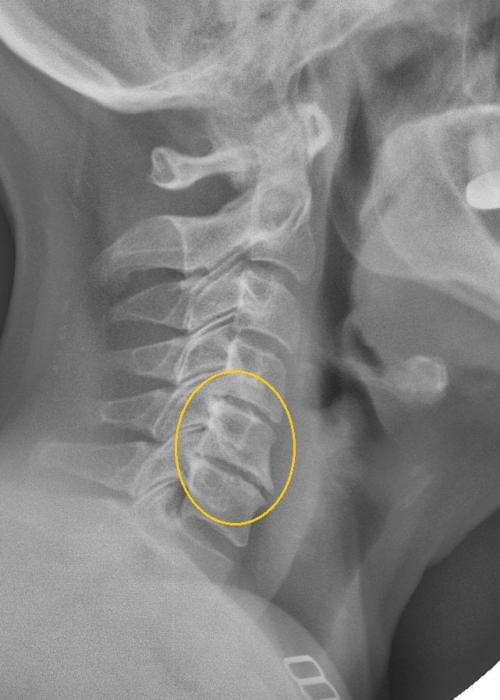

Давит в горле ниже кадыка, что делать. Боль в горле при шейном остеохондрозе: как диагностировать, чем лечить

Боль в горле при остеохондрозе шейного отдела позвоночника.

Казалось бы, нет никакой взаимосвязи между остеохондрозом шеи и болью в горле. Этот симптом характерен для большинства вирусных, бактериальных, грибковых респираторных инфекций — бронхитов, бронхиолитов, острых тонзиллитов. Но боль не исчезает после полоскания антисептическими растворами, рассасывания противовоспалительных пастилок, драже и леденцов. После проведения ряда инструментальных и лабораторных исследований устанавливают причину дискомфорта в горле и гортани. Это остеохондроз, обычно локализованный в шейном отделе позвоночника. Поэтому для устранения болезненных ощущений требуется лечение основной патологии опорно-двигательного аппарата. После ее переведения в стадию устойчивой ремиссии исчезнут першение,, проблемы с проглатыванием пищи.

Диагноз на рентгене.

Боль в горле при шейном остеохондрозе имеет нейровегетативное происхождение, связанное с близкой локализацией верхних дыхательных путей к шейным позвонкам. Остеохондроз — дегенеративно-дистрофическая патология, причина развития которой окончательно не установлена. В результате нарушения диффузного обмена начинают разрушаться хрящевые ткани дисков, дестабилизируя позвонки. Пытаясь сохранить функциональную активность позвоночника, организм запускает процесс формирования костных наростов () для удерживания позвонков в анатомически правильном положении. Острые края разросшихся костных пластинок сдавливают мышцы, кровеносные сосуды. Из-за разрушения дисков быстро сокращается расстояние между позвонками. При соприкосновении они защемляют чувствительные спинномозговые корешки, расположенные между этими костными структурами. Полноценная передача нервных импульсов становится невозможной. Если нервные окончания имеют общую иннервацию с респираторными структурами, то появляются боли в горле при остеохондрозе шейного отдела позвоночника.

Остеохондроз шейного отдела позвоночника не является причиной кома в горле, тем более, если ком в горле — это изолированная жалоба. При остеохондрозе возникает ощущение скованности в шейном отделе позвоночника, но никак не ком в горле. «Вертеброгенный ком в горле» возможен при развитии спондилеза — когда разрастаются огромные спондилофиты (такие костные разрастание в виде шипов), которые давят на глотку. Но это редкое явление. При значительных смещениях позвонков (спондилолистезах) может быть ощущение кома в горле , но тогда будет много других очень неприятных и болевых ощущений, которые отодвинут ощущения кома в горле на последний план.